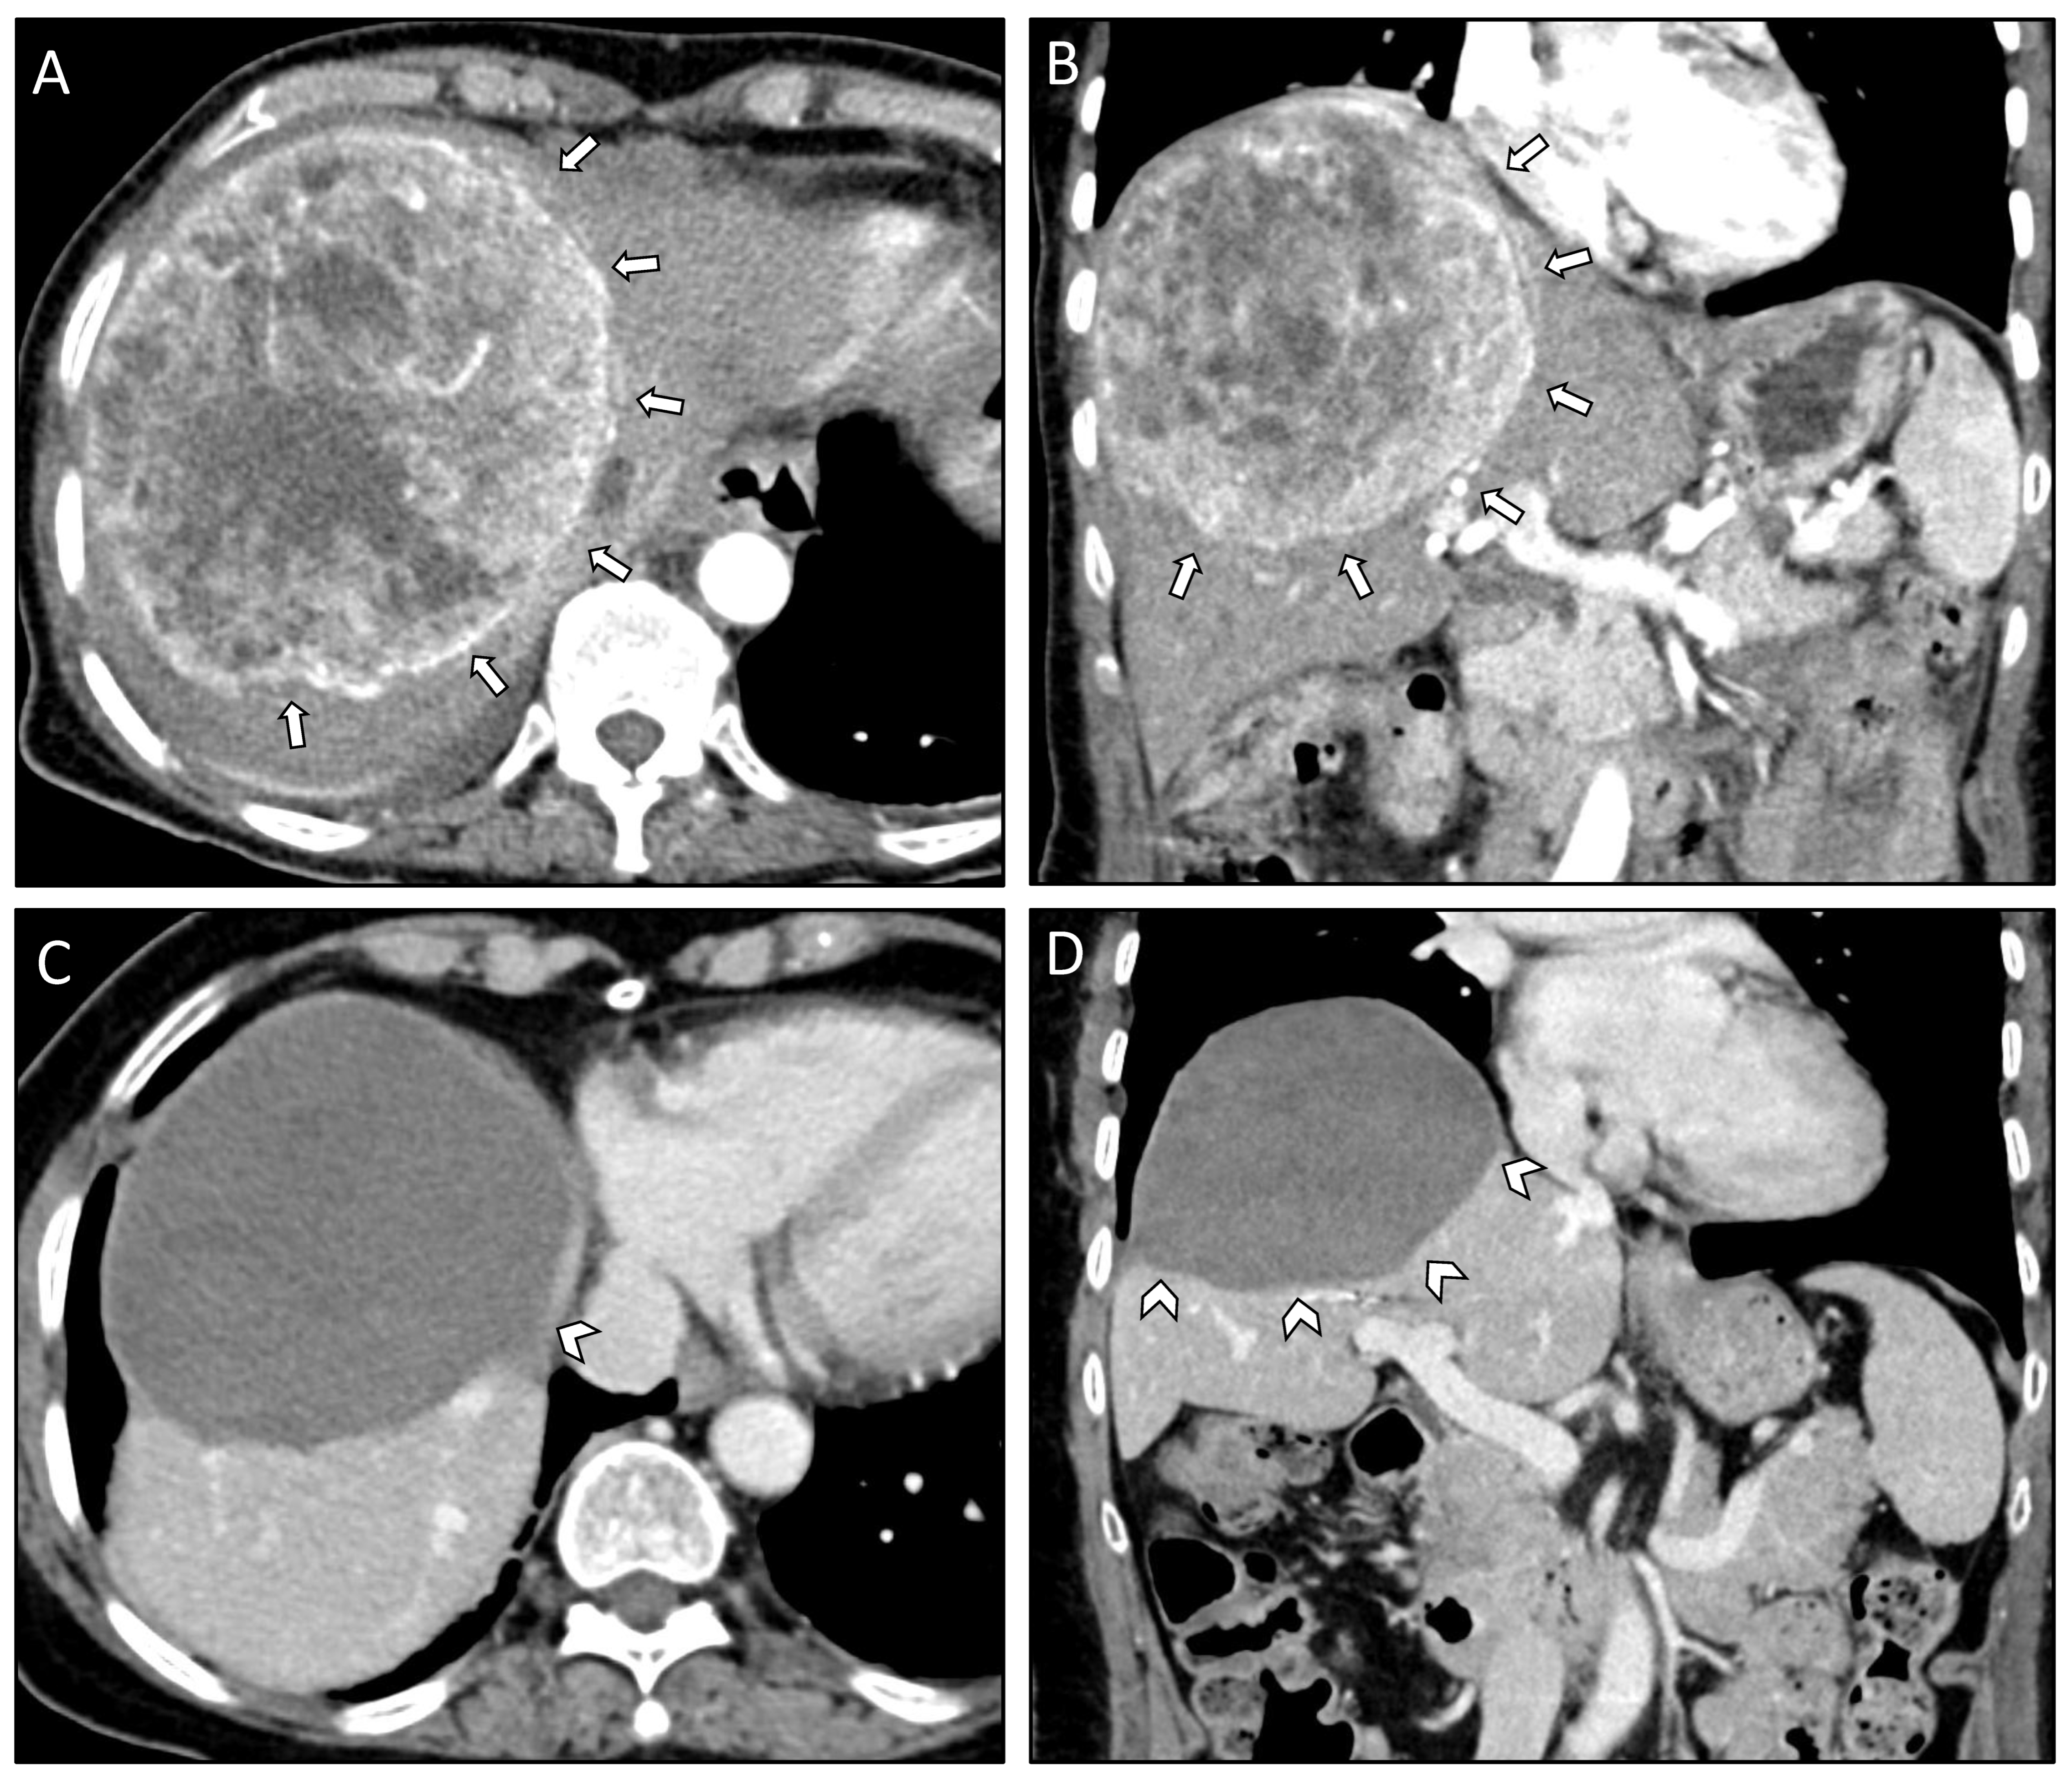

| Case #1 | Treatment | Comments | Liver Segments | Classification | Complications |

| 05.11.2018 | SRFA | 1 lesion, 13 cm, 6 needles, 47 min ablation time | V, VII, VIII | Initial | none |

| 29.11.2018 | SRFA | 1 lesion, 13 cm, 28 needles, 223 min ablation time | VIII | Initial | none |

| 11.12.2018 | SRFA | 1 lesion, 13 cm, 13 needles, 60 min ablation time | V, VII, VIII | Initial | none |

| 28.01.2019 | SRFA | 1 lesion, 13 cm, 15 needles, 43 min ablation time | V, VII, VIII | Initial | none |

| 01.03.2019 | SRFA | 1 lesion, 13 cm, 5 needles, 17 min ablation time | VIII | Local recurrence | none |

| 05.11.2020 | SRFA | 1 lesion, 13 cm, 12 needles, 59 min ablation time | VIII, V | Distant recurrence | none |

| Location at initial diagnosis | Right lobe | Bilobar | Bilobar |

| Number at initial diagnosis | 1 | 3 | 3 |

| Size of largest metastasis at initial diagnosis | 13 cm | 12 cm | 13 cm |